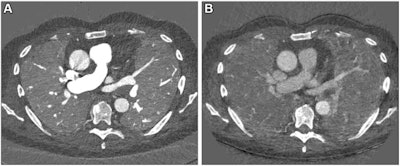

The group conducted a study that included 166 patients with interstitial lung disease and post-COVID conditions; each individual underwent a contrast-enhanced inspiratory PCCT followed by expiratory PCCT after a delay of five minutes between November 2021 and June 2022.

- Mean dose-length product was 110.32 mGy ∙ cm* for the inspiration PCCT and 109.47 mGy ∙ cm, for the expiration PCCT.

- Mean CT dose index for the inspiration exam was 3.22 mGy and for the expiration exam was 3.09 mGy (both of which are less than the mean total radiation dose of 8 mGy to 12 mGy, the diagnostic reference standard).

The PCCT protocol shows promise for other lung imaging applications, such as preoperative evaluation of emphysema and perfusion defects in patients with chronic thromboembolic pulmonary hypertension, according to the authors. After surgery, the PCCT protocol could help clinicians evaluate the success of lung or stem cell transplant procedures.